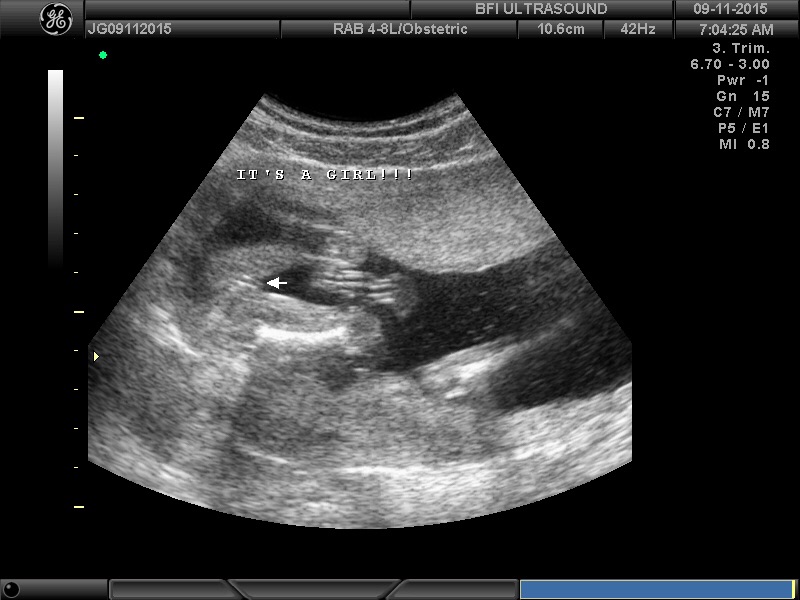

We are having a boy and found out at 16 weeks via ultrasound. Soooo excited but I was sooo sure I was having a girl that I was a bit shocked. Couldn't be happier now and I'm currently 20 weeks